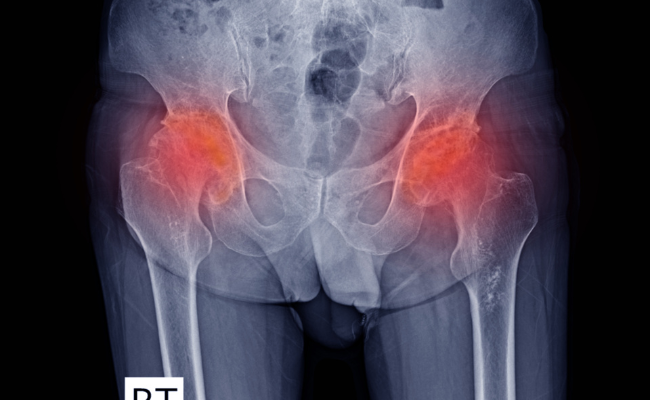

Avascular necrosis, often referred to as osteonecrosis, is a debilitating medical condition in which the bone tissue dies due to a lack of blood supply. This condition can affect various bones in the body, but it most commonly occurs in the hip joint. When bone tissue dies, it can lead to pain, limited mobility, and even bone collapse. Avascular necrosis is a progressive and potentially severe disorder that requires prompt attention and treatment.